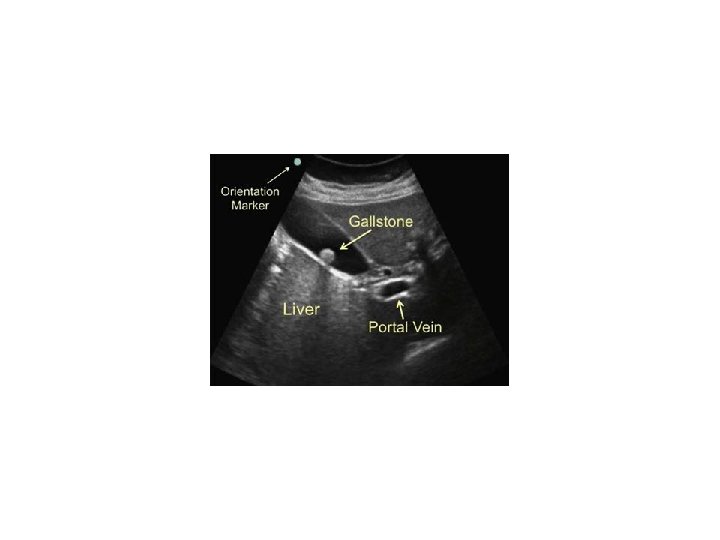

• Hyperechoic – Structure reflects most sound waves – Structure appears white on screen

• Anechoic – Structure allows most sound waves through – Structure appears black on screen

• Echogenic – Tissues in between – Allow some sound waves through and reflect others – Structures appear in various shades of gray depending on amount of reflection